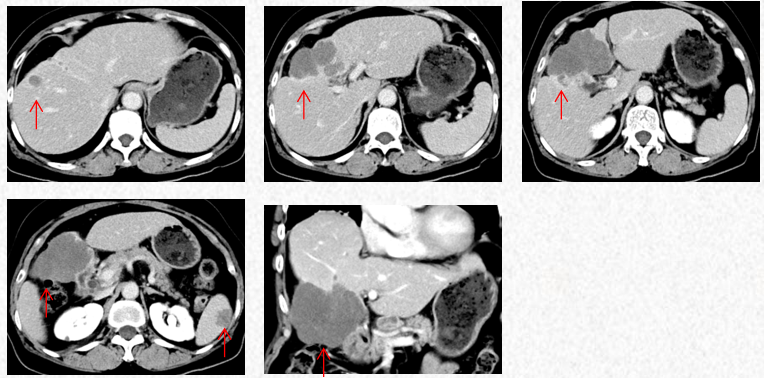

2023-3-19复查胸腹CT图片,最佳疗效评估为PR。

2023-5-22复查胸腹CT图片,疗效评估为SD,出现轻度双上肢麻木,可耐受。

2023-7-15复查胸腹CT图片,疗效评估为SD,轻度双上肢麻木,生活不受影响。

2023-3-19胸腹CT:肝肿物最大横截面积91*60mm,脾脏转移瘤(19*12mm)

2023-5-22胸腹CT:肝肿物最大横截面积86*58mm,脾脏转移瘤(19*12mm)

2023-7-15胸腹CT:肝肿物最大横截面积86*58mm,脾脏转移瘤(19*12mm)